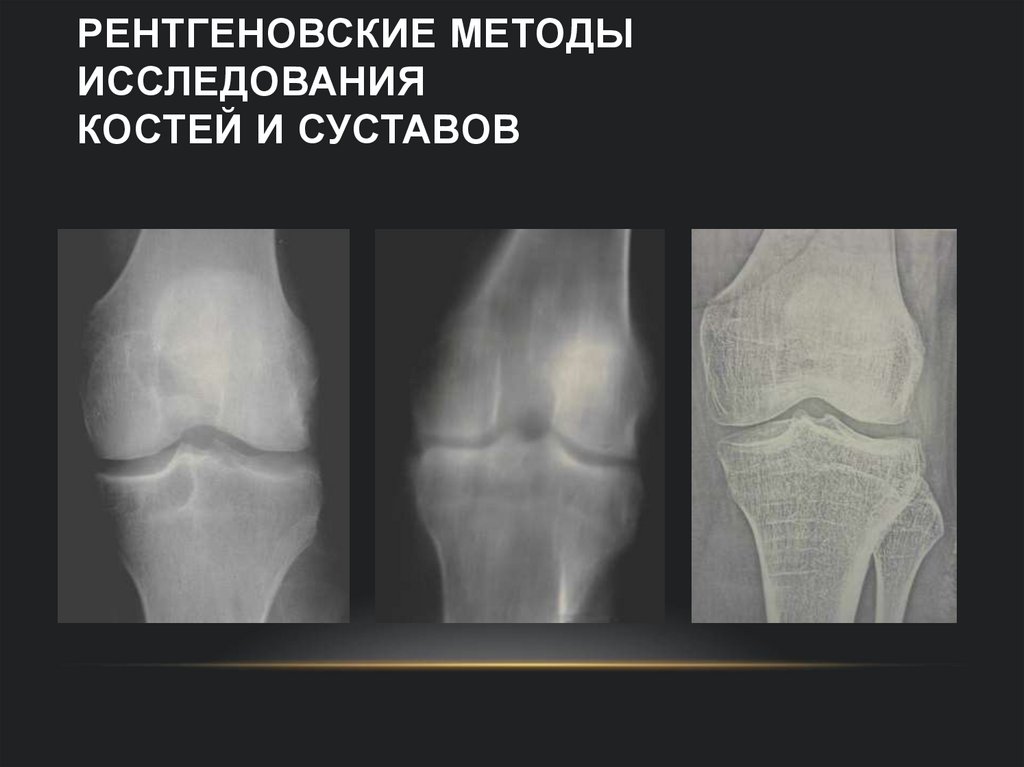

4. Рентгеновские методы исследования костей и суставов

РЕНТГЕНОВСКИЕ МЕТОДЫ

ИССЛЕДОВАНИЯ

КОСТЕЙ И СУСТАВОВ

5. Рентгенография коленного сустава в 2-х проекциях

РЕНТГЕНОГРАФИЯ КОЛЕННОГО СУСТАВА В 2-Х

ПРОЕКЦИЯХ

Показаниями могут быть любые повреждения и травмы,